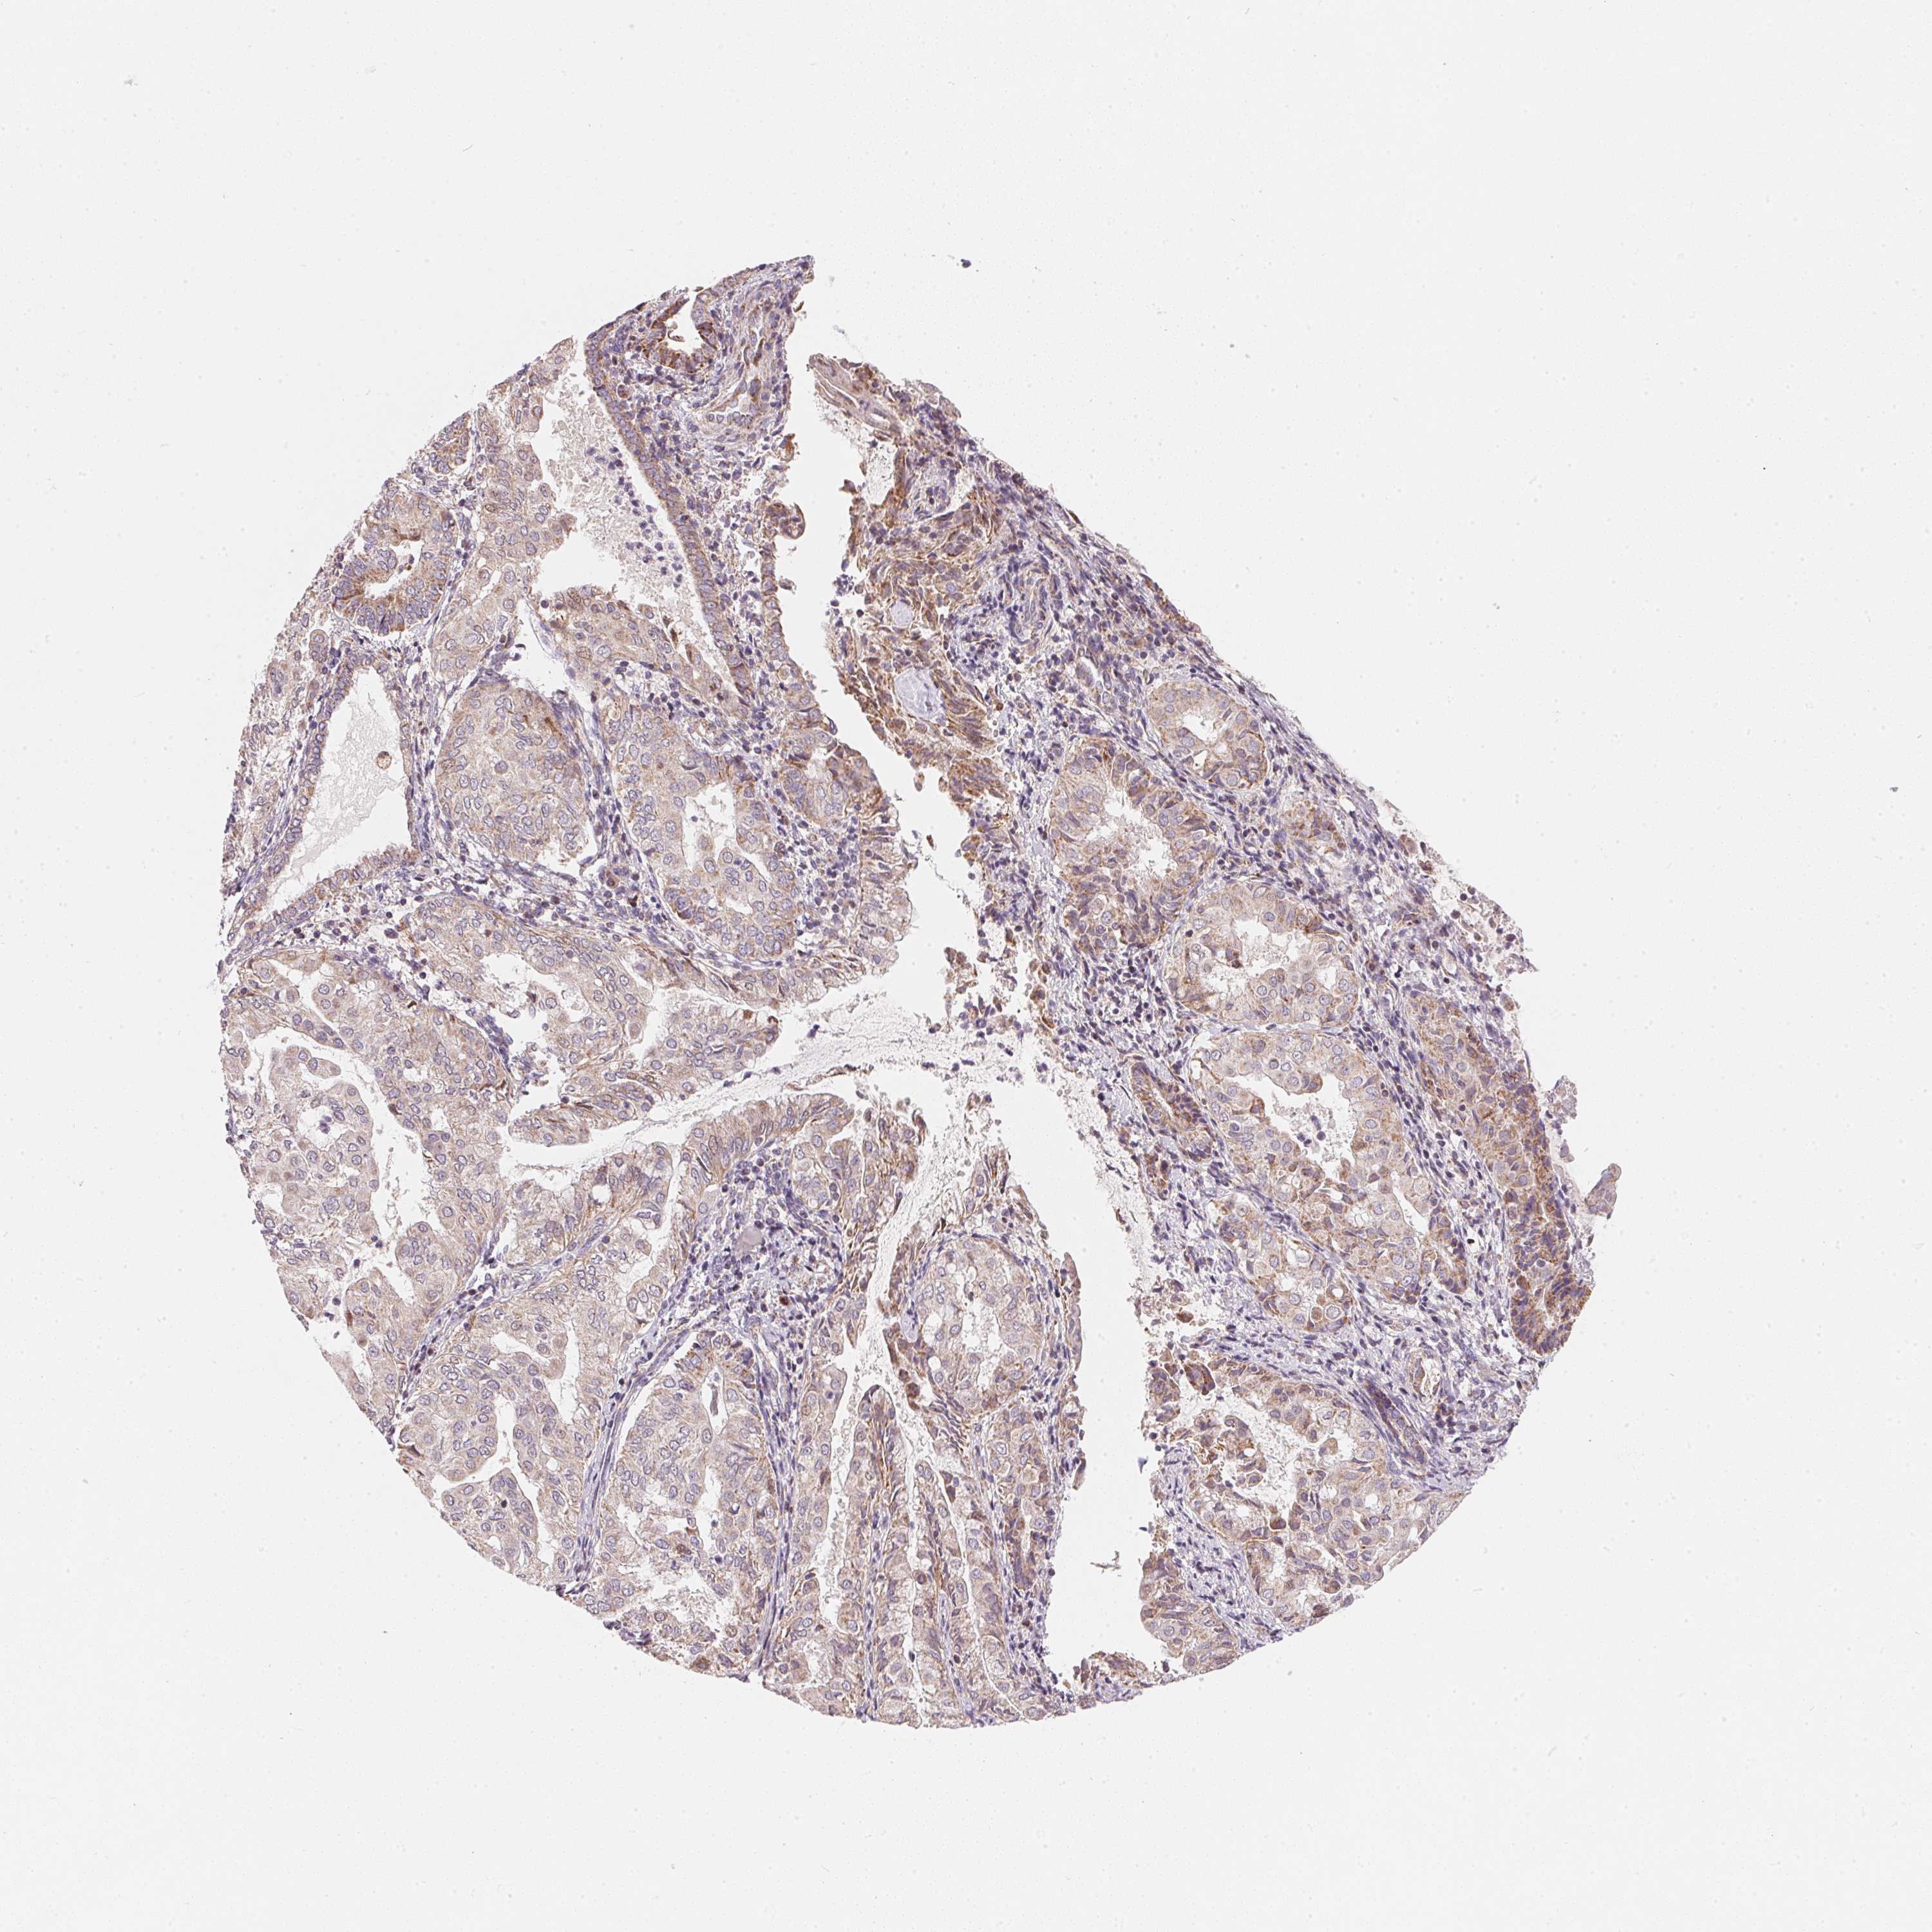

ENDOMETRIAL CANCER - Protein expressioni

A mouse-over function shows sample information and annotation data. Click on an image to view it in a full screen mode. Samples can be filtered based on level of antibody staining by selecting one or several of the following categories: high, medium, low and not detected. The assay and annotation is described here.

Note that samples used for immunohistochemistry by the Human Protein Atlas do not correspond to samples in the TCGA dataset.

Antibody stainingi

Antibody staining in the annotated cell types in the current human tissue is reported as not detected, low, medium, or high, based on conventional immunohistochemistry profiling in selected tissues. This score is based on the combination of the staining intensity and fraction of stained cells.

Each image is clickable and will lead to virtual microscopy that enables deeper exploration of all samples and also displays staining intensity scores, fraction scores and subcellular localization as well as patient and tissue information for each sample.

Antibody HPA067252

Staining

High

Medium

Low

Not detected

Intensity

Strong

Moderate

Weak

Negative

Quantity

>75%

75%-25%

<25%

None

Location

Nuclear

Cytoplasmic/membranous

Cytoplasmic/membranous,nuclear

Adenocarcinoma, NOS

Adenocarcinoma, metastatic, NOS